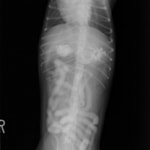

単純レントゲン検査:胃内ガス陰影・腸内ガスが少量認められる。

嘔吐が改善しないため、消化管バリウム造影検査を実施。

消化管バリウム造影レントゲン

バリウム造影3時間経過するも、胃内からバリウム排泄なく同日内視鏡検査を実施。